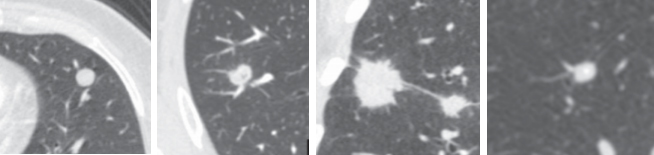

理想的方法需要结合患者的临床特征(年龄、吸烟史、癌症家族史、恶性肿瘤史)、CT的结节征象(大小、钙化、针刺状、分叶状、胸膜退缩、边缘清楚、和孔腔)和生物标志物检测结果。这些特性中的一些可以帮助评估恶性肿瘤的概率。目前,已经有一些生物学模型结合使用这些特征的来鉴别SPN。虽然这些模型在报告的研究中的准确性基本上是可以接受的,但是缺乏一个大型的队列来进行验证的。一个结合临床特征、CT征象和生物标志物的诊断模型需要在数千人的大队列中开发和验证,这样的结果才可能具有更好的临床应用潜力。

④ 结节的形状:园的、 分叶的、 不规则的如针刺状的;